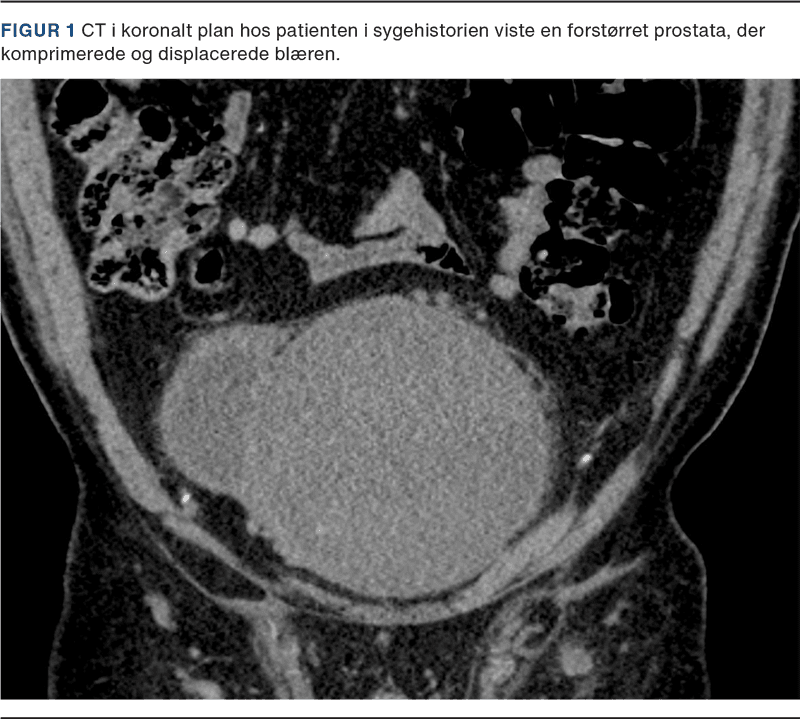

En 68-årig mand med markant forstørret prostata (1.500-1.700 cm3) (Figur 1), som displacerede blæren, blev henvist på grund af problemer med at udføre selvkateterisering. Han havde kronisk urinretention behandlet med intermitterende kateterisering og ingen tidligere urinvejsinfektioner. Han fik medicin mod hypertension og hyperkolesterolæmi. Efter udredning blev PAE tilbudt. S-kreatininniveauet var normalt, og patienten blev opstartet i behandling med 5-alfa-reduktasehæmmer (finasterid) to måneder før indgrebet. Han indtog ikke nefrotoksiske farmaka op til behandlingen.